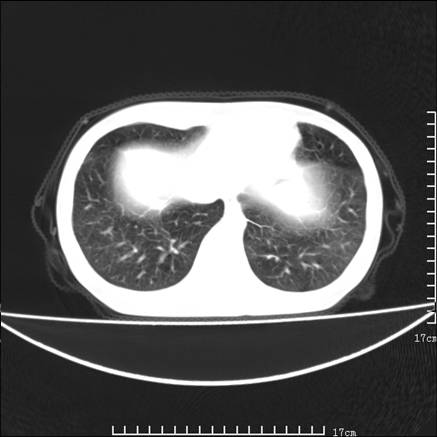

女,46岁,患胃溃疡多年,溃疡大小约1.0cm左右,后于5年前手术,病理为胃癌。主诉:半月前感冒后胸闷,气短,有咳嗽,无明显咳痰,无发热。偶有腰背部不适。

以下为高分辨扫描图像

双肺小叶间增厚,双肺散布粟米影和磨玻璃状影,以双肺上叶为重。结合病史考虑转移(癌性淋巴细管炎)可能性大。

结合病史:认为是典型肺部癌性淋巴管炎、淋巴结转移。请看图解。

正如caihe主任所言,影像表现结合临床病史应该支持肺癌性淋巴管炎;上肺大片边缘不清的渗出病变,多系感染所致,临床有感冒病史并咳嗽表现。肺癌性淋巴管炎临床一般无咳嗽、咳痰症状。